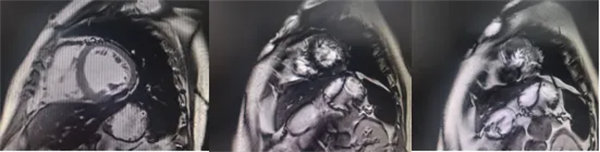

心肌信號局部減低 呈現“黑色心肌”表現,這是由于鐵沉積導致局部磁場不均勻,引起信號丟失(失相位)。

肝臟和脾臟信號改變 矢狀位梯度回波定位圖像可顯示肝臟和脾臟信號降低,提示肝脾鐵沉積,T2*>6.3及R2*>160/s表現中度鐵過載。